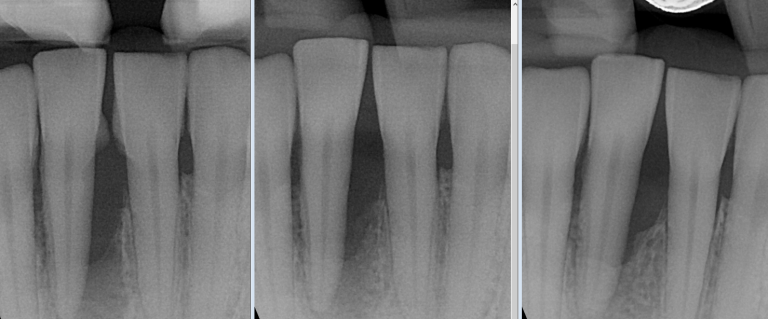

Chirurgie parodontale

Pour traiter les parodontites avancées (infections des gencives et de l’os):

Lambeaux parodontaux (nettoyage en profondeur sous la gencive)

Greffes de gencive pour recouvrir une racine exposée

Greffe osseuse parodontale pour régénérer l’os perdu